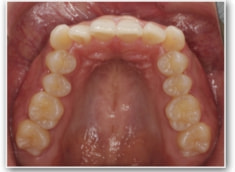

治療前